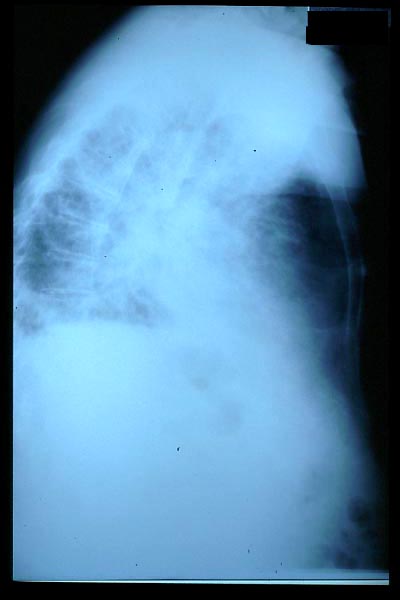

Fibrosis pulmonar. ICC.